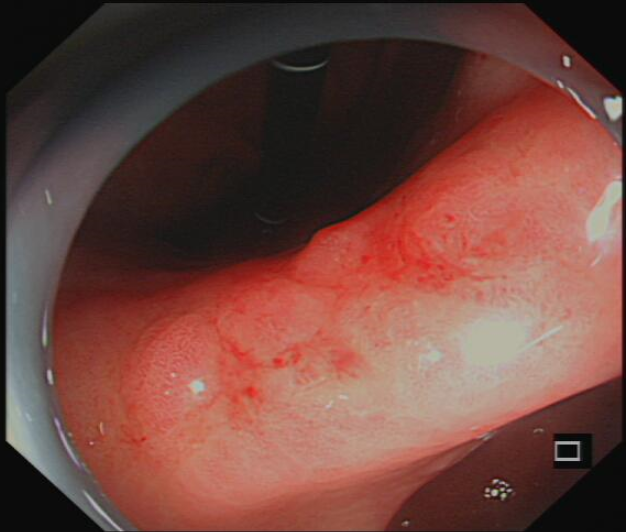

图1胃镜:白光下病变表现

ESD术前进行内镜精查发现病变胃镜白光下,NBI放大观察及靛胭脂染色,病变均符合内镜下胃早癌表现。胃角病变是ESD操作最困难部位,随着充气的增多,镜身会远离胃角,不容易接近病变,增加了剥离难度,术中又发现病变中央存在纤维化粘连,为手术剥离增加了风险,唐印华教授凭借精湛的技术和丰富的腔镜经验,利用牙线—钛夹牵引,增加了黏膜下层的空间,使黏膜下视野充分暴露,且镜身更容易接近病变,大大提高了剥离的速度,使手术快速顺利结束。